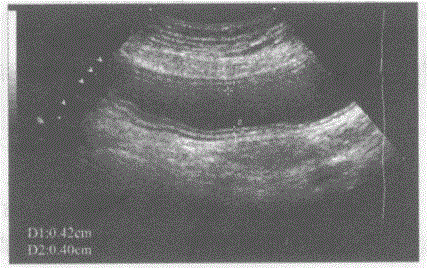

问题 临床资料:男,27岁,常规体检。 超声综合描述:剑突下扫查可见长圆形无回声区,边界清晰,呈5层结构,壁厚0.4cm。 超声提示:

选项 A.正常胃壁声像图 B.腹腔包裹性积液 C.肠系膜囊肿 D.胰腺假性囊肿

答案 A